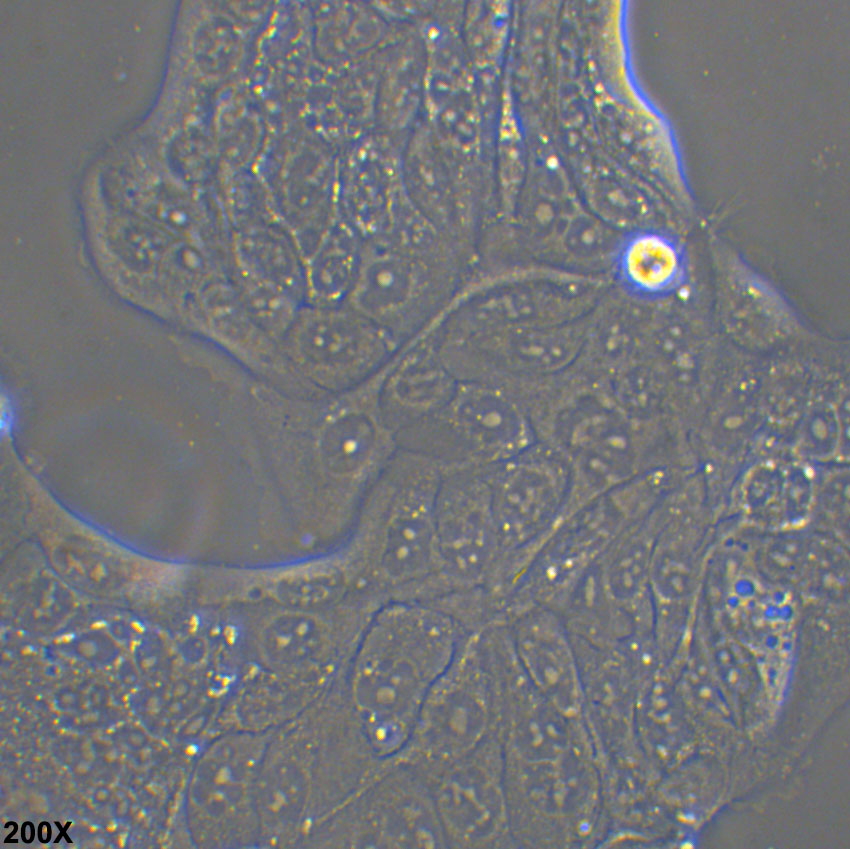

形态特征 上皮细胞样

生长特征 贴壁

培养要点 细胞成片生长,且生长速度较慢